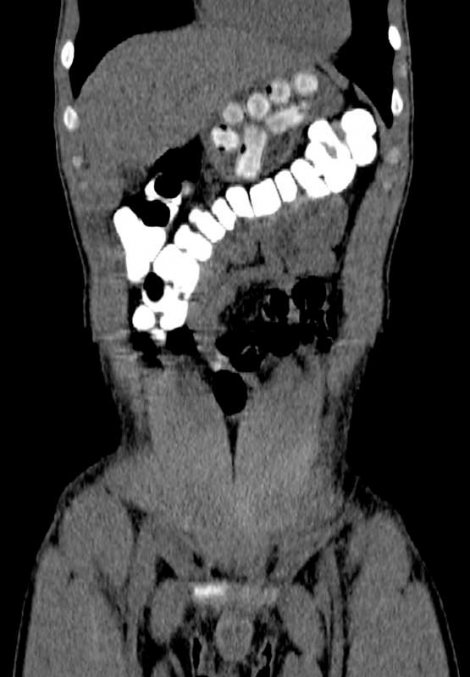

Уапсениот веднаш бил однесен во болница за да му бидат извадени пакетчињата со дрога кои ги проголтал во Африка. Шверцерите кои на ваков начин пренесуваат дрога се нарекуваат „муле“, и се во состојба да ја носат дрогата во стомак и по неколку дена. На тој начин можат да пренесат и до килограм дрога. Уапсениот немал кривично досие во Србија.